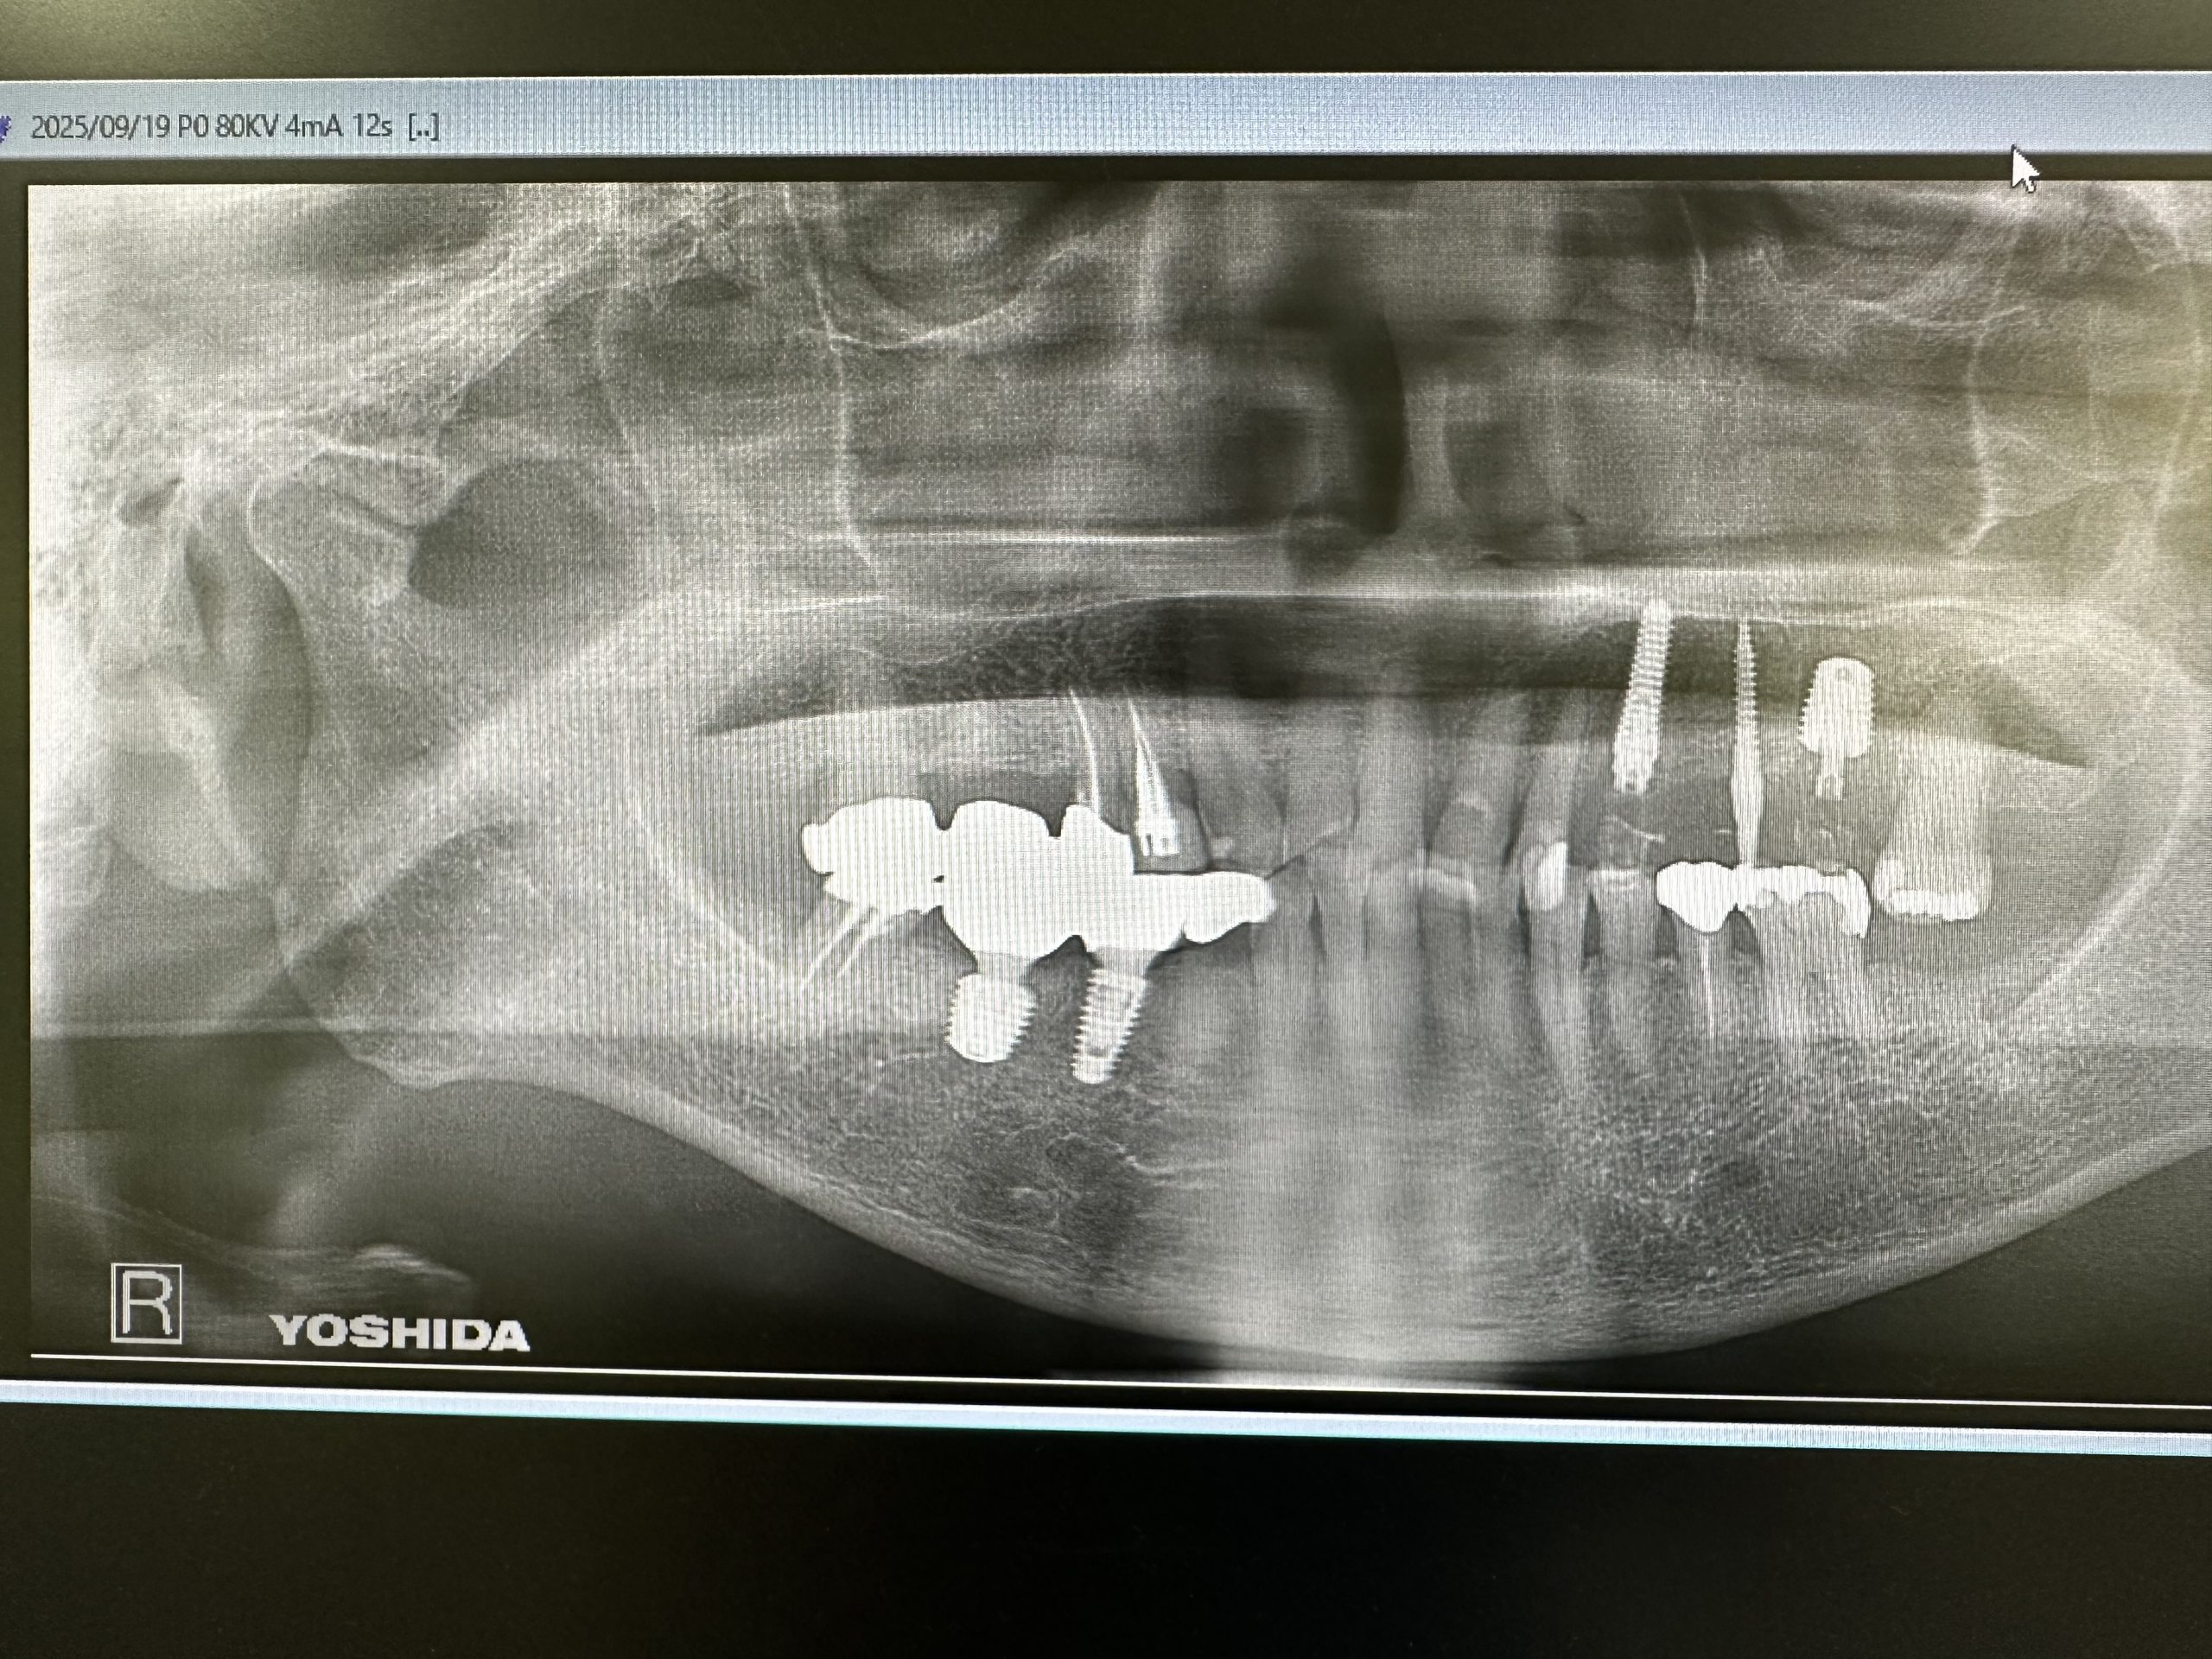

本日は昼からインプラントオペ

昨年右下オペした方

今回は反対側の上顎3.6番

2本抜歯、6番はソケットリフト、いわゆるデンサーリフト💪

採血し遠心分離機13分、CGFメンブレン作成

暫間インプラントも併用、色々と工夫しながらダネ!

計測値も良く、一安心